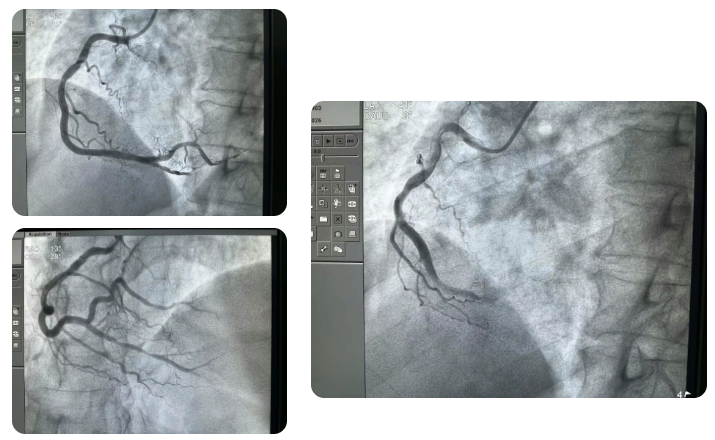

70 岁的周大叔突发剧烈胸痛被送往巫溪县人民医院,入院时心电图提示急性下壁心梗并伴有心动过缓,心率指标持续偏低,生命体征极不稳定。杨俊杰接到会诊通知后即刻到场,启动胸痛中心绿色通道,为患者开通急诊介入治疗通道。急诊冠脉造影检查结果显示,患者粗大的右冠远段完全闭塞,这是导致其心梗和心动过缓的根本原因。

时间就是心肌,在维持患者生命体征稳定的同时,杨俊杰带领当地介入团队迅速开展介入手术,凭借丰富的临床经验和娴熟的操作技巧,精准定位闭塞血管部位,顺利开通闭塞的右冠血管,恢复冠脉血流灌注。术后,患者的胸痛症状瞬间缓解,心率也逐步恢复至正常水平,从死亡线上被成功拉回,家属悬着的心终于落了地。